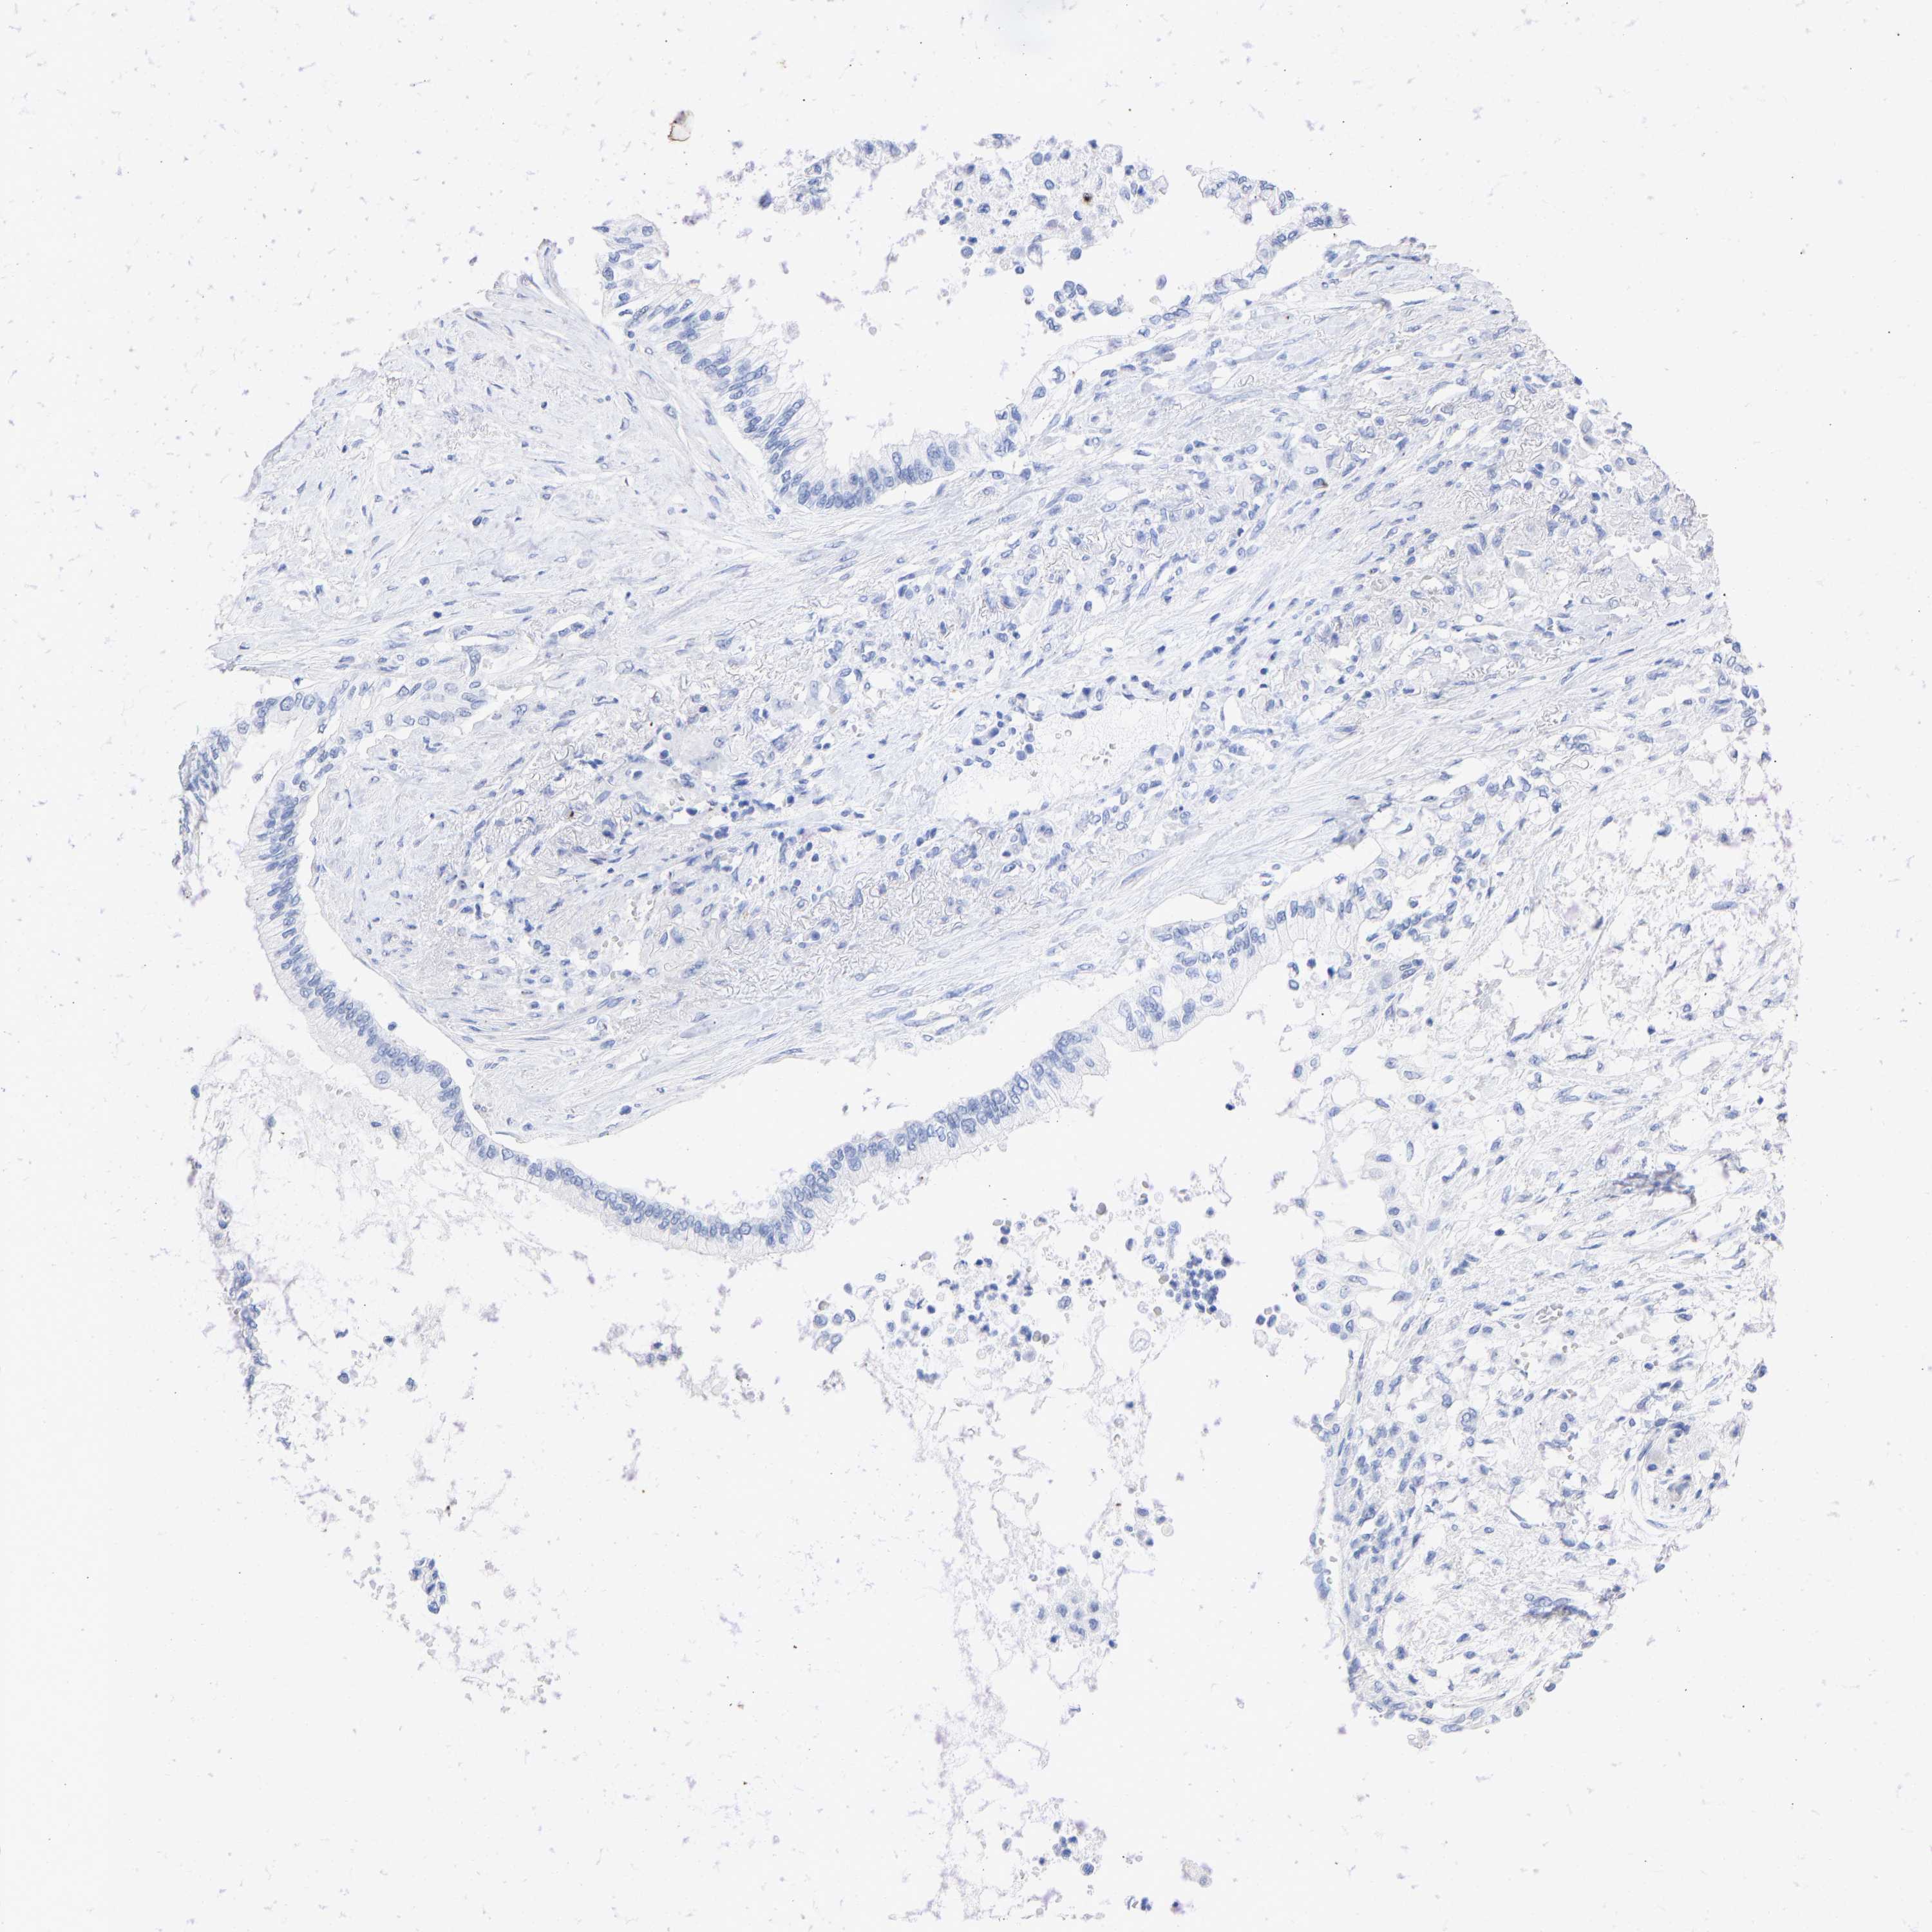

PANCREATIC CANCER - Protein expressioni

A mouse-over function shows sample information and annotation data. Click on an image to view it in a full screen mode. Samples can be filtered based on level of antibody staining by selecting one or several of the following categories: high, medium, low and not detected. The assay and annotation is described here.

Note that samples used for immunohistochemistry by the Human Protein Atlas do not correspond to samples in the TCGA dataset.

Antibody stainingi

Antibody staining in the annotated cell types in the current human tissue is reported as not detected, low, medium, or high, based on conventional immunohistochemistry profiling in selected tissues. This score is based on the combination of the staining intensity and fraction of stained cells.

Each image is clickable and will lead to virtual microscopy that enables deeper exploration of all samples and also displays staining intensity scores, fraction scores and subcellular localization as well as patient and tissue information for each sample.

Antibody HPA017917

Antibody HPA062908

Antibody CAB002153

Adenocarcinoma, NOS